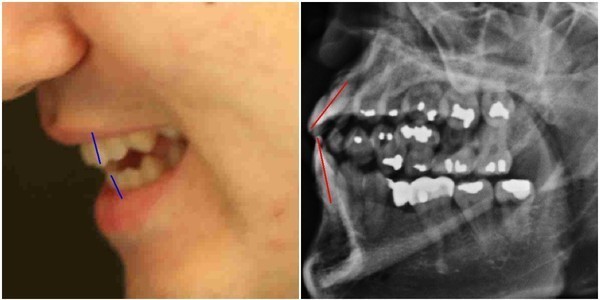

- ▲ 양승오 박사와 치과의사 김우현씨 등, ‘박주신씨 병역비리 의혹’을 제기하고 있는 시민들이, 의혹을 뒷받침하는 근거 중 하나로 지목하고 있는 박주신씨의 치아가 보이는 엑스레이 사진. ⓒ 뉴데일리DB

주신씨의 치아가 보이는 엑스레이에서 드러나는 석연치 않은 의혹, 주신씨의 치아를 치료했다고 주장하는 전 참여연대 운영위 부위원장 출신 치과의사가 검찰에 제출한 증거자료에서 나타나는 ‘유령건강보험증’ 사용 내역, 주신씨 공개신검 당일 현장을 촬영한 서울시 직원의 동영상이 중요 부분에서 편집된 사실 등도, 이 사건 피고인들이 제시하고 있는 주요 증거들이다.

- ▲ ▲ 박주신씨의 치아 상태를 알수 있는 엑스레이 사진 자료. ⓒ 뉴데일리DB

- ▲ ▲ 박주신 엑스레이(X-RAY)에 대한 치의학 박사의 분석자료. ⓒ 뉴데일리DB

양승오 박사 등에 대한 검찰의 수사가 진행되던 지난해, 이 사건 피고인들은 박주신씨 치아 X-Ray를 근거로, 박주신씨의 신체를 촬영했다는 X-Ray 속 피사체가 제3의 인물일 가능성을 주장했다.

주신씨의 치아 X-Ray는 허리 MRI 촬영 과정에서 찍힌 X-Ray 사진들 중에서 치아가 보이는 X-Ray 사진이다.

따라서 치아 X-Ray 상에 나타나는 각종 의혹은, 허리 MRI와 더불어 해당 피사체가 주신씨가 아닐 가능성에 무게를 더한다.

피고인들이 치아 X-Ray를 근거로, '피사체 바꿔치기' 의혹을 강하게 제기한 이유는, X-Ray에 나타난 치아의 상태가, 도저히 20대 중반 청년의 것이라고는 보기 힘든 특징을 갖고 있었기 때문이다.

주신씨 치아 X-Ray 사진을 보면, 치아 상태가 매우 불량하다는 사실을 알 수 있다. 치아 2개는 아예 없고, 아말감으로 때운 치아가 무려 14개에 달한다.

수은증기 방출 논란으로 문제가 되고 있는 아말감(Amalgam) 치료는 여러 가지 단점을 갖고 있어 사용빈도가 크게 줄고 있다는 것이 치과의료계의 공통된 평가다.

서울 방배동에 사는 중산층 청년이, 치과의사는 물론 환자들도 기피하는 아말감을 이용한 치과 치료를 이처럼 많이 받았다는 것은, 쉽게 받아들이기 어렵다는 것이 이들의 지적이다.

더욱 의심이 가는 부분은 주신씨의 경우, 하악 좌측 1소구치(아래쪽 좌측 첫 번째 작은 어금니)까지 아말감으로 치료했다는 사실이다.

이런 경우는 매우 드물다는 것이 치과의사들의 일반적인 견해다.

이 사건 피고인 중 한명인 치과의사 김우현씨는, 주신씨의 영구치가 맹출을 시작했을 것으로 추정되는 1990년대 중반 이후, 젊은 사람이 1소구치들을 포함한 구치부 치아 전체를 아말감으로 치료했다고 보기엔 무리가 있다고 지적했다.

치의학 박사 C씨는 뉴데일리와 기자와의 인터뷰에서 “주신씨의 전체적인 치료 상태를 보면, 소위 말하는 '야매'로 했을 가능성이 높다”고 밝혔다.

“(주신씨의 것이라고 알려진 구외 X-Ray 사진을 보면) 최근 국내에서 교육받은 치과의사의 치료라고 생각할 수 없을 정도.”

“(주신씨 구외 X-Ray 사진 상의) 45번, 46번 보철치료 및 치아 상실 문제도 마찬가지다. 보철물로는 상당히 저렴한 비귀금속 합금을 사용한 것으로 보인다. 37번 치아는 아예 없는 상태로 방치하기도 했다.”

“박주신씨의 가정환경을 고려하면, 이런 치료를 받았을 가능성은 1%도 안 된다. 서울 방배동에 거주했던 중산층 이상의 가정에서는 흔치 않은 상황.”

주신씨의 치아 아말감 치료와 관련돼, 김우현씨는 “혹자는 아말감 치료를 10개 이상 한 게 무슨 대수냐? 하면서 무시하는 경향이 있지만, 이는 모든 인과관계와 사실들을 무시하려는 것”이라고 비판했다.주신씨의 치아 X-Ray 사진 상에 나타나는 의문들은, 양승오 박사 등이 주신씨의 병역비리 의혹을 제기하게 된 핵심 요인 중 하나였다.

김우현씨는 박주신씨가 자생병원에서 MRI를 촬영하면서 함께 찍은 엑스레이 사진에 의문을 나타냈다.

박주신씨의 치아가 보이는 ‘구외 엑스레이’(이하 치아 엑스레이) 사진에서 나타나는 피사체의 치아상태는 불량하기 짝이 없었다.

도저히 중산층 가정의 20대 청년의 것으로 볼 수 없을 만큼 치아상태가 나빴다.

- ▲ 박주신씨 명의의 치아 엑스레이 사진. ⓒ 뉴데일리DB

김우현씨는 서울 방배동에 살던 20대 청년이 무려 14개에 이르는 치아를 아말감으로 치료 하고, 일부 치아는 아예 빠진 채 몇 년간 방치된 사실에 고개를 가로저었다.

아말감은 수은증기 논란과 변색의 문제점 등으로 1990년대 들어 사용빈도가 급감했다. 2005년경 서울의 중산층 청년이 하나도 아닌 무려 14개의 치아를 아말감으로 치료한다는 것은 상식 밖이었다.

김우현씨는 치과의사로서의 임상경험을 근거로, 자생병원 엑스레이 피사체의 정체에 의문을 가졌다.